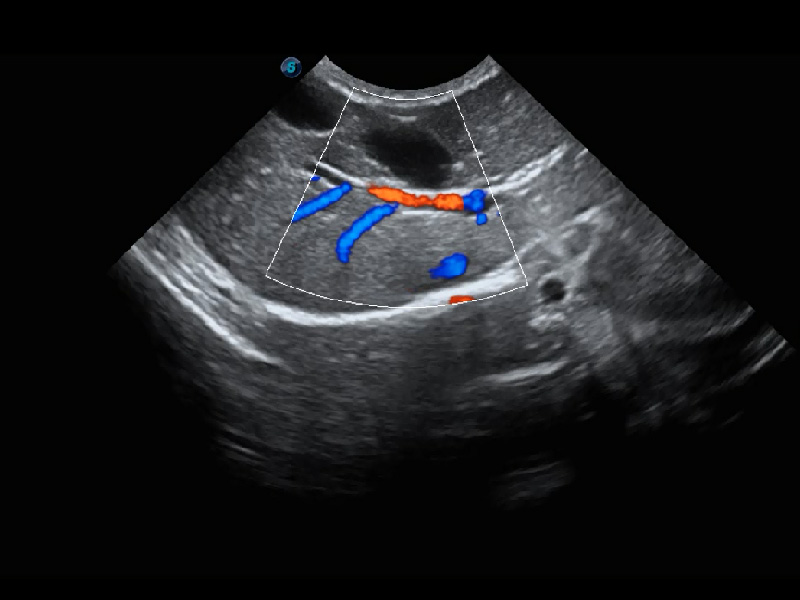

ProPet 60 作为一款高端台式动物超声设备,为动物医生的日常诊断提供了一系列贴合动物临床需求、解决临床实际问题的高级成像功能。凭借全系列高清探头,满足医生对腹部、心脏、生殖、浅表、肌骨等成像的所有需求,切实帮助您提升检查效率,提高诊断信心。

动物是人类最亲密的朋友和最值得信赖的伙伴。乐玩lewin国际也一直致力于探索动物专用的超声影像解决方案。 全新推出的ProPet系列,是乐玩lewin国际在动物超声影像智能化、专业化、精准化的一次跨越式革新。动物不能用言语来表述自己的不适,通过超声影像,ProPet系列搭建了动物医生与不同物种沟通的“桥梁”,为动物医生注入了“治愈之力”。